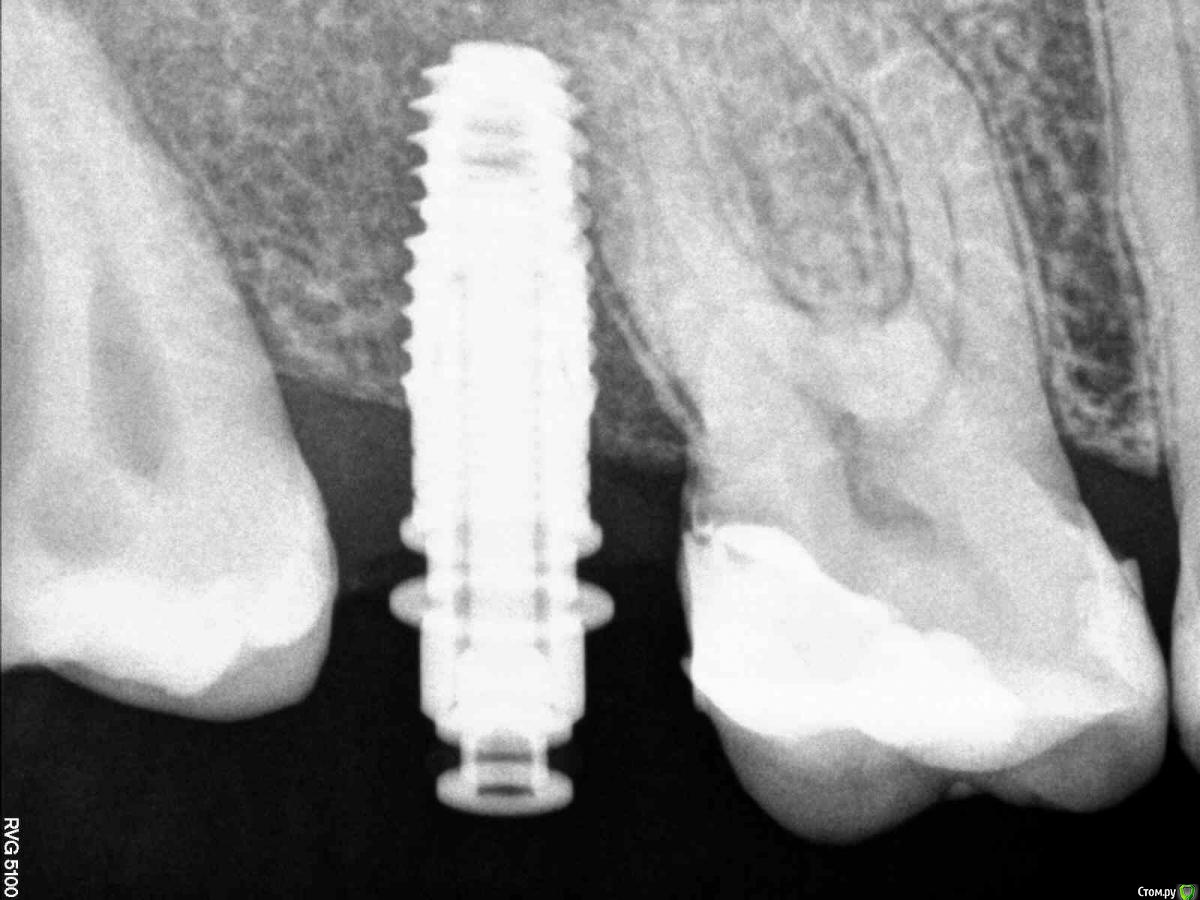

Кариес+ Опубликовано 8 августа, 2016 Поделиться Опубликовано 8 августа, 2016 Установил имплантат осстем , на контрольном рг увидел что очень близко к корню, изменил угол и вышло так как на втором снимке. Будут ли проблемы при протезировании? Ссылка на комментарий

Nazim_NV86 Опубликовано 8 августа, 2016 Поделиться Опубликовано 8 августа, 2016 TS3 4.0x8.5 ?Трансфер не войдёт. Формик пробовали прикрутить? Ссылка на комментарий

Кариес+ Опубликовано 8 августа, 2016 Автор Поделиться Опубликовано 8 августа, 2016 Импл 4/8.5 ts3 osstem. Формик не прикручивал , но сам имплантовод не упирался Ссылка на комментарий